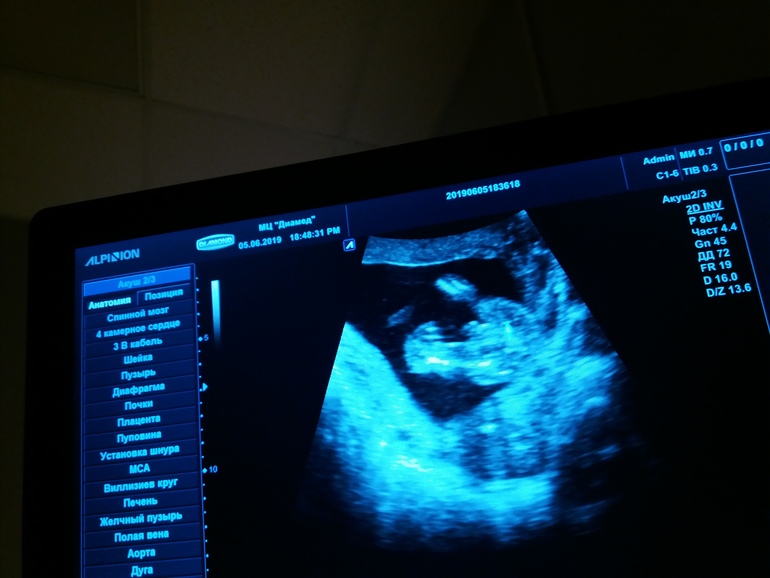

исутствовала на узи

Присутствовала на узи 118 фотографий

Диамед 24